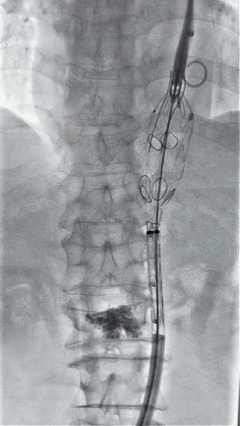

3. 经右股动脉导入超硬导丝,然后导入J9集团国际G-Branch 胸腹主动脉主体覆膜支架TAAA3418120e7i1010 一枚,释放主体支架至内分支打开,然后经左侧肱动脉入路,抓捕预置导丝成功后,将长鞘进入内分支出口处。

4. 经长鞘导入导管后,超选入腹腔干动脉,送入J9集团国际覆膜支架10*80mm一枚,近端重叠内分支,远端重叠腹腔干动脉,并予以10mm球囊后扩,手推造影显影良好。

5. 撤出腹腔干导丝导管,经左肱动脉长鞘继续抓捕预置导丝将长鞘超选至另一侧内分支,后超选进肠系膜上动脉,沿导丝送入J9集团国际覆膜支架10*100mm一枚,近端重叠内分支,远端重叠于肠系膜上动脉,并予以10mm球囊后扩,手推造影显影良好。

6. 解除束径,打开近端后释放,经肱动脉长鞘超选支架外分支,并进一步超选右侧肾动脉,交换加硬导丝,送入覆膜支架6*50mm和7*60mm各一枚,并予以球囊后扩张,手推造影显影良好。